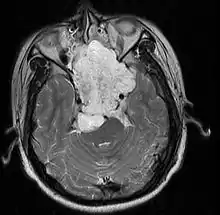

- Skull base:

- May be intracranial or extracranial, with mass effect symptoms depending on location

- Headaches and/or facial pain are common

- Pituitary insufficiency, hemianopsia/diplopia, cranial nerve deficits, nasal stuffiness.

Skull Base